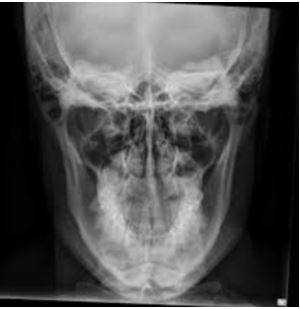

- Рентгенография околоносовых пазух. Позволяет визуализировать кистозные образования в виде округлой тени внутри пневматизированной полости синуса. Для максимальной информативности снимки выполняются в двух проекциях. При необходимости исследование проводится с контрастным усилением.

Полученный результат рентген-снимка оценивают исключительно в одной плоскости, что не дает развернутой картины происходящего. Костные образования могут заходить друг за друга, и рентгенолог не всегда может четко отличить накладывающиеся изображения.

КТ, напротив, дает объемную трехмерную модель органа, верхнюю и нижнюю челюсть можно оценить сразу в нескольких проекциях и посмотреть даже внутреннюю структуру костей.

Рентгеновский снимок челюсти